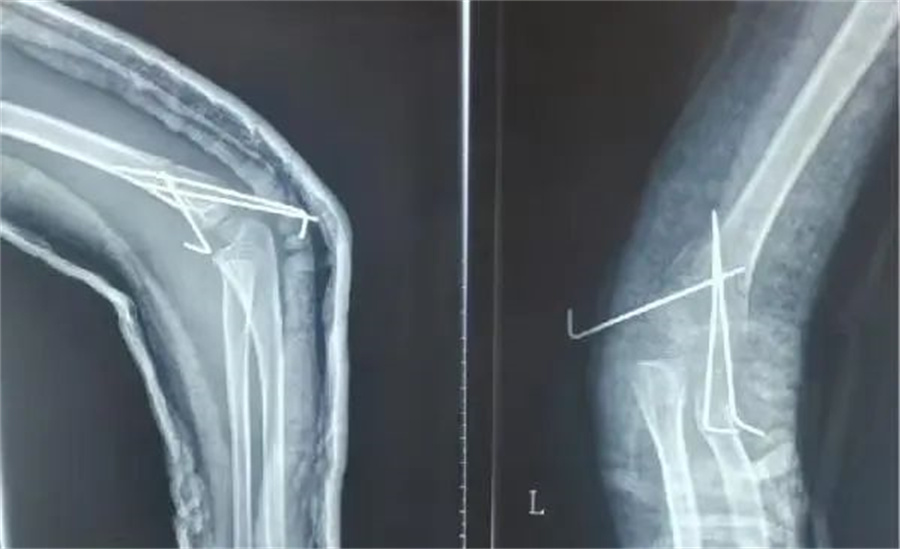

在各项检查指标都正常的情况下,儿童医院骨科的医护人员为他做了髁上骨折闭合复位术。

正常情况下,这属于常规手术。但是由于诚瑞太胖,胳膊又短又粗,复位的时候摸不到骨头,无形中增加了手术难度。

骨科医生在放射线下,一点一点摸索,最终复位成功,并且术后没有切口,没有瘢痕,4天后,孩子顺利出院。